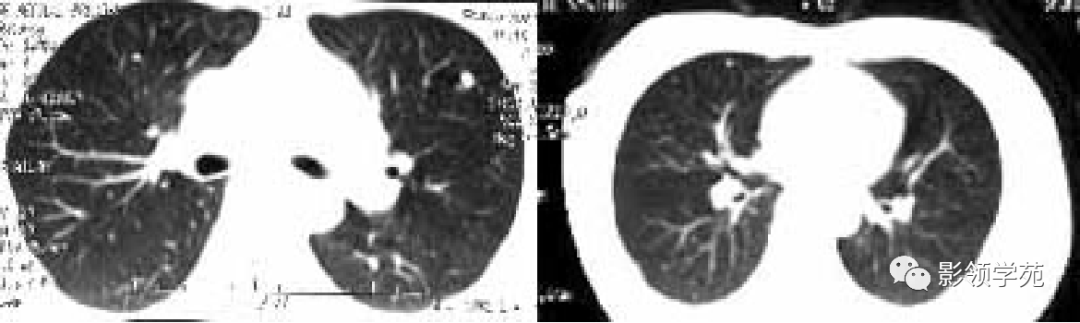

肿瘤外科患者,女55,9月前阴道不规则流血,诊刮术病检:子宫内膜浆液性腺癌(IV期),肺转移癌,盆腔淋巴结转移,骨转移,晚期无手术可能,省肿瘤TC方案化疗4周期,我院PAC方案化疗3疗程。

瘤外科患者,女,48,左乳癌根治术后2月术后化疗。病理:左乳伴髓样癌特征的乳腺浸润性导管癌。术后TAC方案化疗1个周期。

左乳切除术后,左肺下野两个大小不等高密度影。